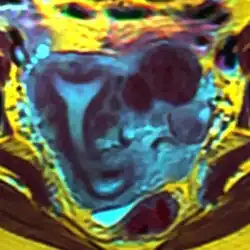

Der Uterus arcuatus („bogenförmige Gebärmutter“) ist eine angeborene anatomische Veränderung der Gebärmutter (Uterus), die bei fehlender Funktionsstörung lediglich als Variante oder als milde Form einer Fehlbildung, des Uterus bicornis bzw. Uterus septus angesehen werden kann.[1][2]

Die Gebärmutterhöhle (Cavum uteri) ist im Fundus (Gebärmutterkuppe) nicht gerade oder konvex (nach außen), sondern konkav (nach innen gewölbt), die Muskelschicht (Myometrium) formt ein angedeutetes Septum.[1]

Die Diagnose kann mittels Sonografie und/oder Kernspintomographie gestellt werden.